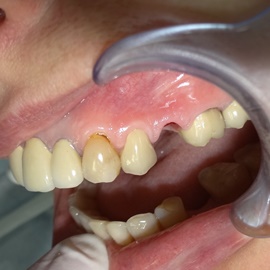

Przedtrzonowce często należą do okolicy estetycznej należy więc zwrócić wzmożona uwagę na poprawną anatomię tkanek kości i dziąsła. Po utracie zęba 25 pacjentka kilka lat chodziła bez jego uzupełnienia, doszło do przesunięcia się zęba 26. U tej pacjentki przed laty był wykonany most jednobrzeżny na czwórce, dość szybko doszło jednak do przeciążenia zęba filarowego, zaniku kości wyrostka i wreszcie pęknięcia korzenia zęba filarowego mostu. Po ekstrakcji i wygojeniu kości stwierdzono ubytek kości wyrostka przekraczający objętość 50% stanu początkowego. Stąd główny nacisk położono na odbudowę tkanek. Uzyskano zadowalający wynik anatomiczny.

Podstawą do uzyskania korzystnych wyników leczenia są diagnostyka, określenie planu leczenia i staranne wykonanie wszystkich etapów leczenia. Tutaj przykład pacjentki, u której nie dopilnowano poprawnych stosunków pionowych, przy implantacji. Konieczne było leczenie korekcyjne.

Pacjentka lat 41, odbudowa protetyczna zębów 24, 25 na implantach - korony porcelanowe na metalu. Po stronie prawej zdjęto most 13 - 16, poprawiono warunki kostne wyrostka zębodołowego i wykonano most na implantach od czwórki do szóstki, oraz nacementowano pojedynczą koronę na kła.

Pacjentka lat 50. Most od zęba 24 do zęba 27. Pękł korzeń zęba filarowego 24. Po ekstrakcji wykonano zabieg odbudowy kości wyrostka zębodołowego i podniesiono zatokę. Następnie po skorygowaniu kształtu i objętości dziąsła przytwierdzonego wykonano pojedyńcze korony na implantach 24, 26, oraz most 13-17